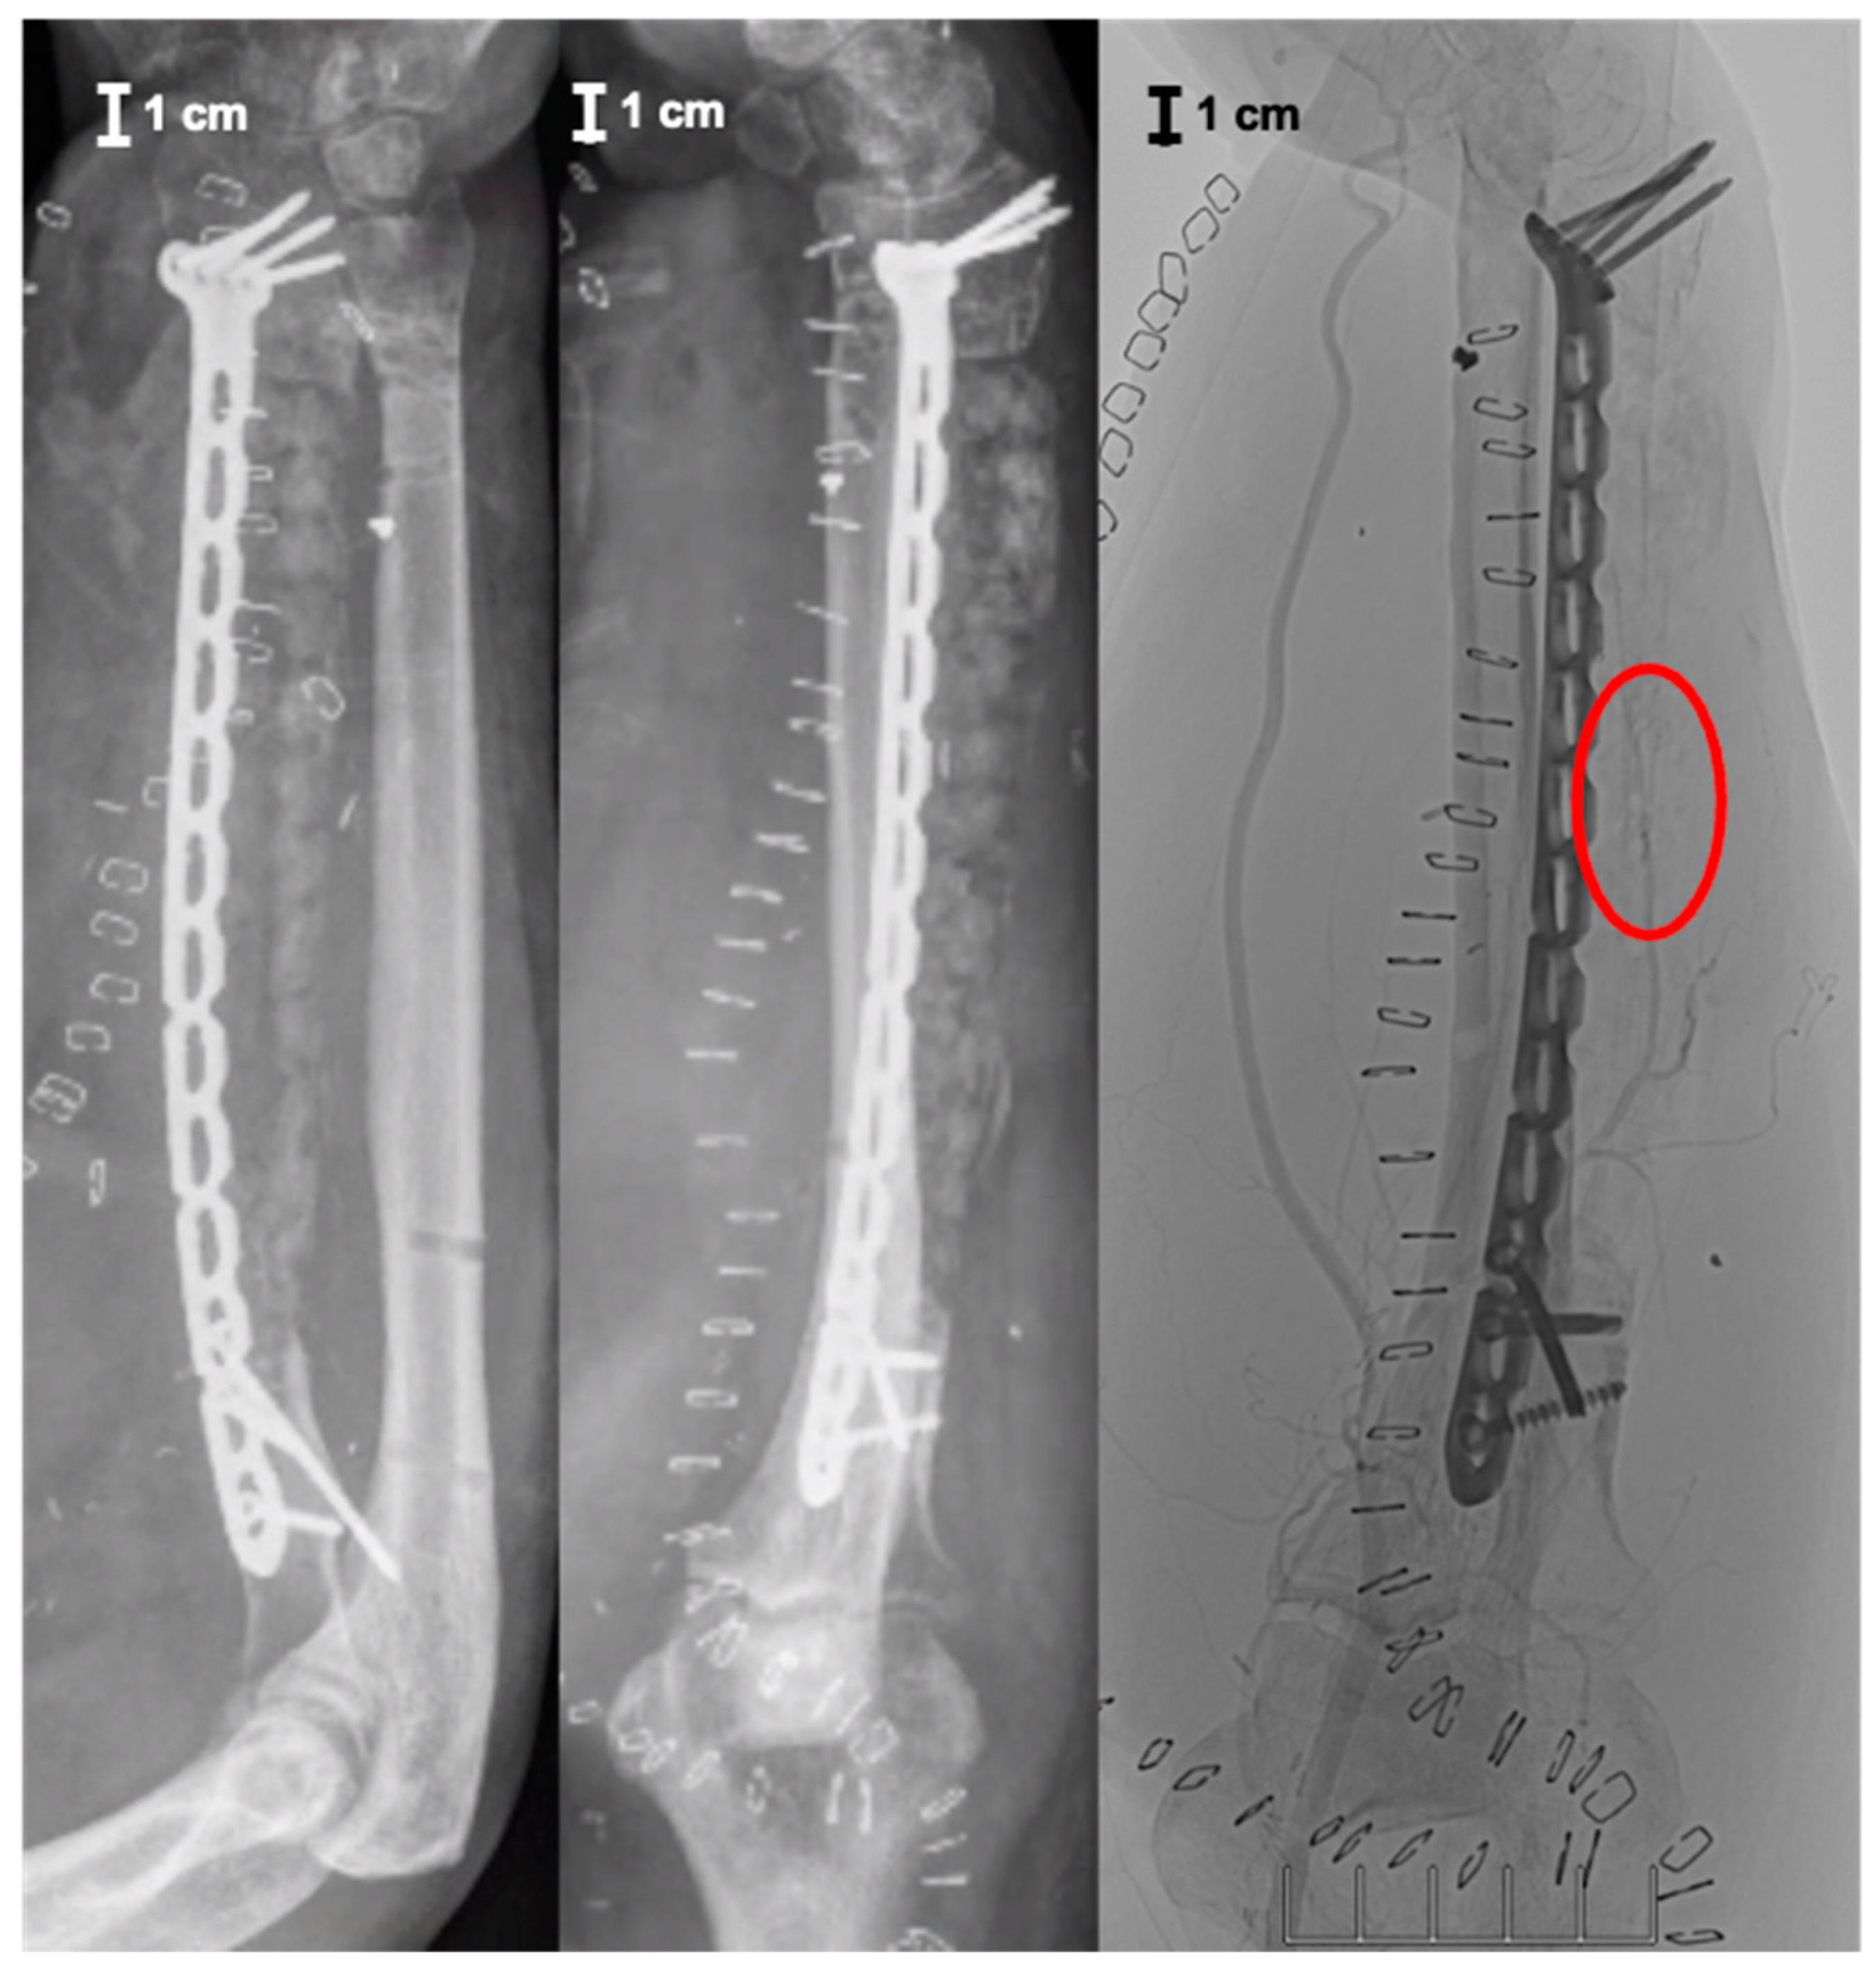

2. Case Report